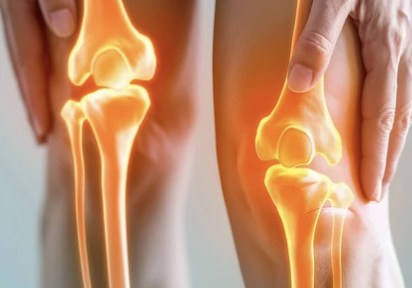

무릎 연골은 뼈와 뼈 사이에서 완충 작용을 하여 관절의 부드러운 움직임을 돕고, 마찰을 줄여주는 역할을 해요.

- 연골의 종류: 무릎에는 반월상 연골과 관절 연골, 두 가지 종류의 연골이 있어요. 반월상 연골은 무릎 안쪽과 바깥쪽에 C자 모양으로 위치하며, 충격 흡수와 안정성 유지에 중요한 역할을 합니다. 관절 연골은 뼈 끝 부분을 덮고 있으며, 뼈끼리 부딪히는 것을 막아주고 부드러운 움직임을 가능하게 해요.